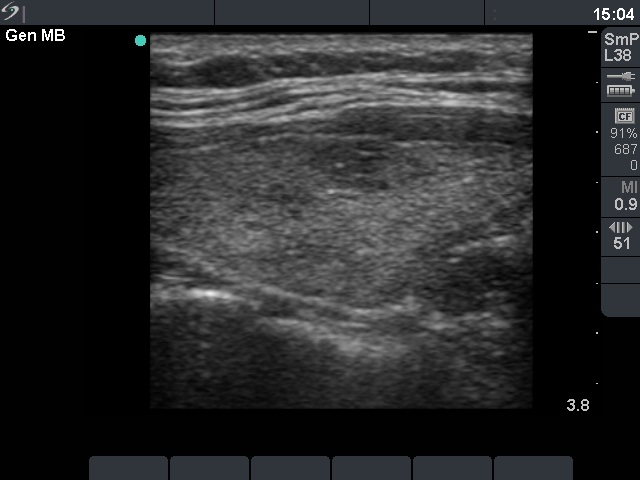

Hashimoto thyroiditis - Case 61

Right lobe, longitudinal view

Compare the two series of pictures. Hashimoto's thyroiditis frequently has a similar appearance as observed in the case of de Quervain's thyroiditis. The patchy appearance i.e. hypoechogenic areas within an echonormal background is observed in around 70% of the former, while in more than 90% of the latter disease. In contrast with subacute thyroiditis, the hypoechogenic areas in most of the Hashimoto's cases have irregular but sharp borders. In the cases demonstrated above, the only difference between the ultrasound appearance is the pattern of the hypoechogenic areas. These foci are more blurred in the case of subacute thyroiditis. Nevertheless, the sonographic pattern itself is not diagnostic.